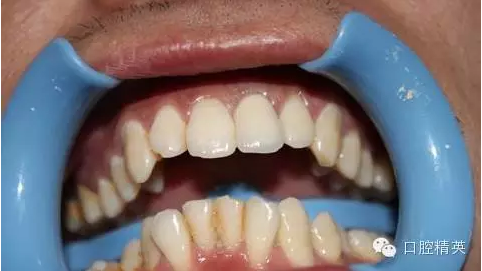

7:試戴烤瓷牙,鈷鉻瓷牙,瓷肩臺處理

8:頸緣檢查

9:完全就位

10:黏結(jié)后,側(cè)面觀